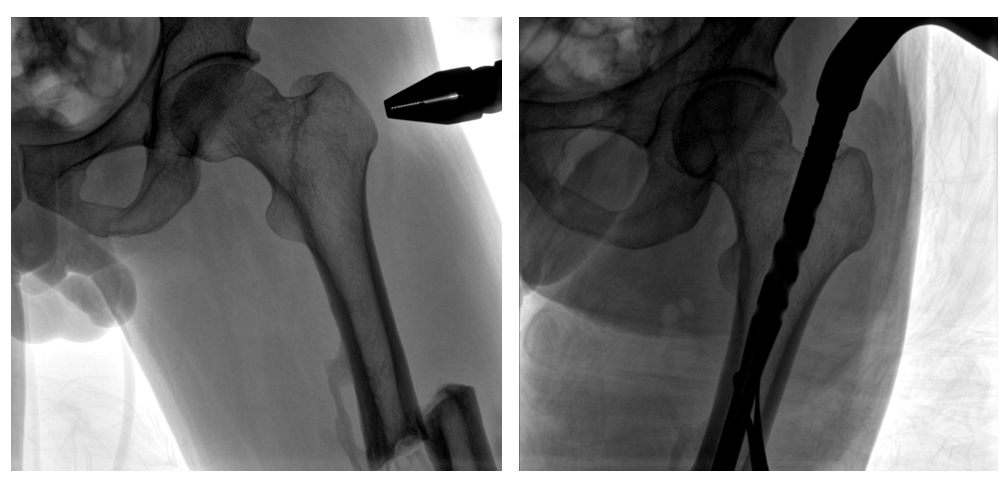

普愛醫(yī)療PLX119C大平板一體式C形臂采用30CM×30CM的平板探測器,在脊柱和長骨骨折等骨科手術治療中,獲取更大視野、更清晰的骨折部位圖像,能夠有助于醫(yī)生在術中及時了解和評估骨折部位的對位、對線情況,且能進行長度和角度測量,為進一步提高手術質(zhì)量提供強有力的支持。